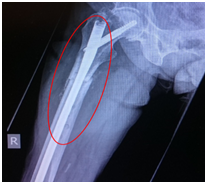

An 83-year-old woman presented to our hospital with low-energy trauma resulting in pain on the right thigh causing an inability to bear weight. She has a history of chronic obstructive pulmonary disease, type 2 diabetes mellitus, gastro esophageal reflux disease, and osteoporosis. She had an intertrochanteric fracture in the right neck of her femur in 2010 that was internally fixed using a dynamic hip screw (DHS) with a two-hole plate (Figure 1) (Figure 2). She was started on alendronate therapy in 2011 for osteoporosis. She had a fracture in the left distal radius in 2013 and underwent manipulation under anesthesia and Kirschner wire fixation. She experienced low-energy trauma in January 2015 and presented with right thigh pain and was unable to bear weight.

Figure 1 Dynamic hip screw with two-hole plate for neck of femur fracture.

Figure 2 Subtrochanteric femur fracture (denoted by a red circle).